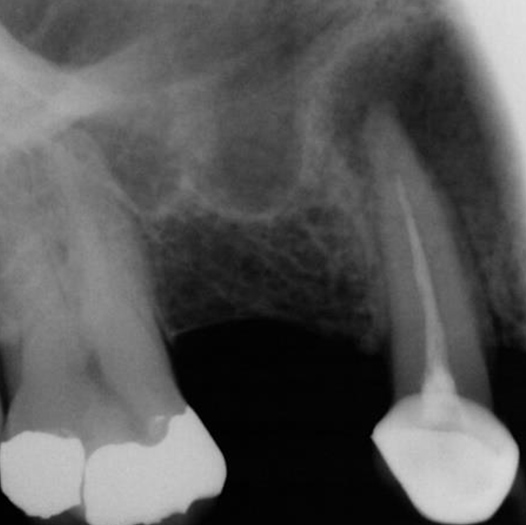

Before

Before Root Canal treatment